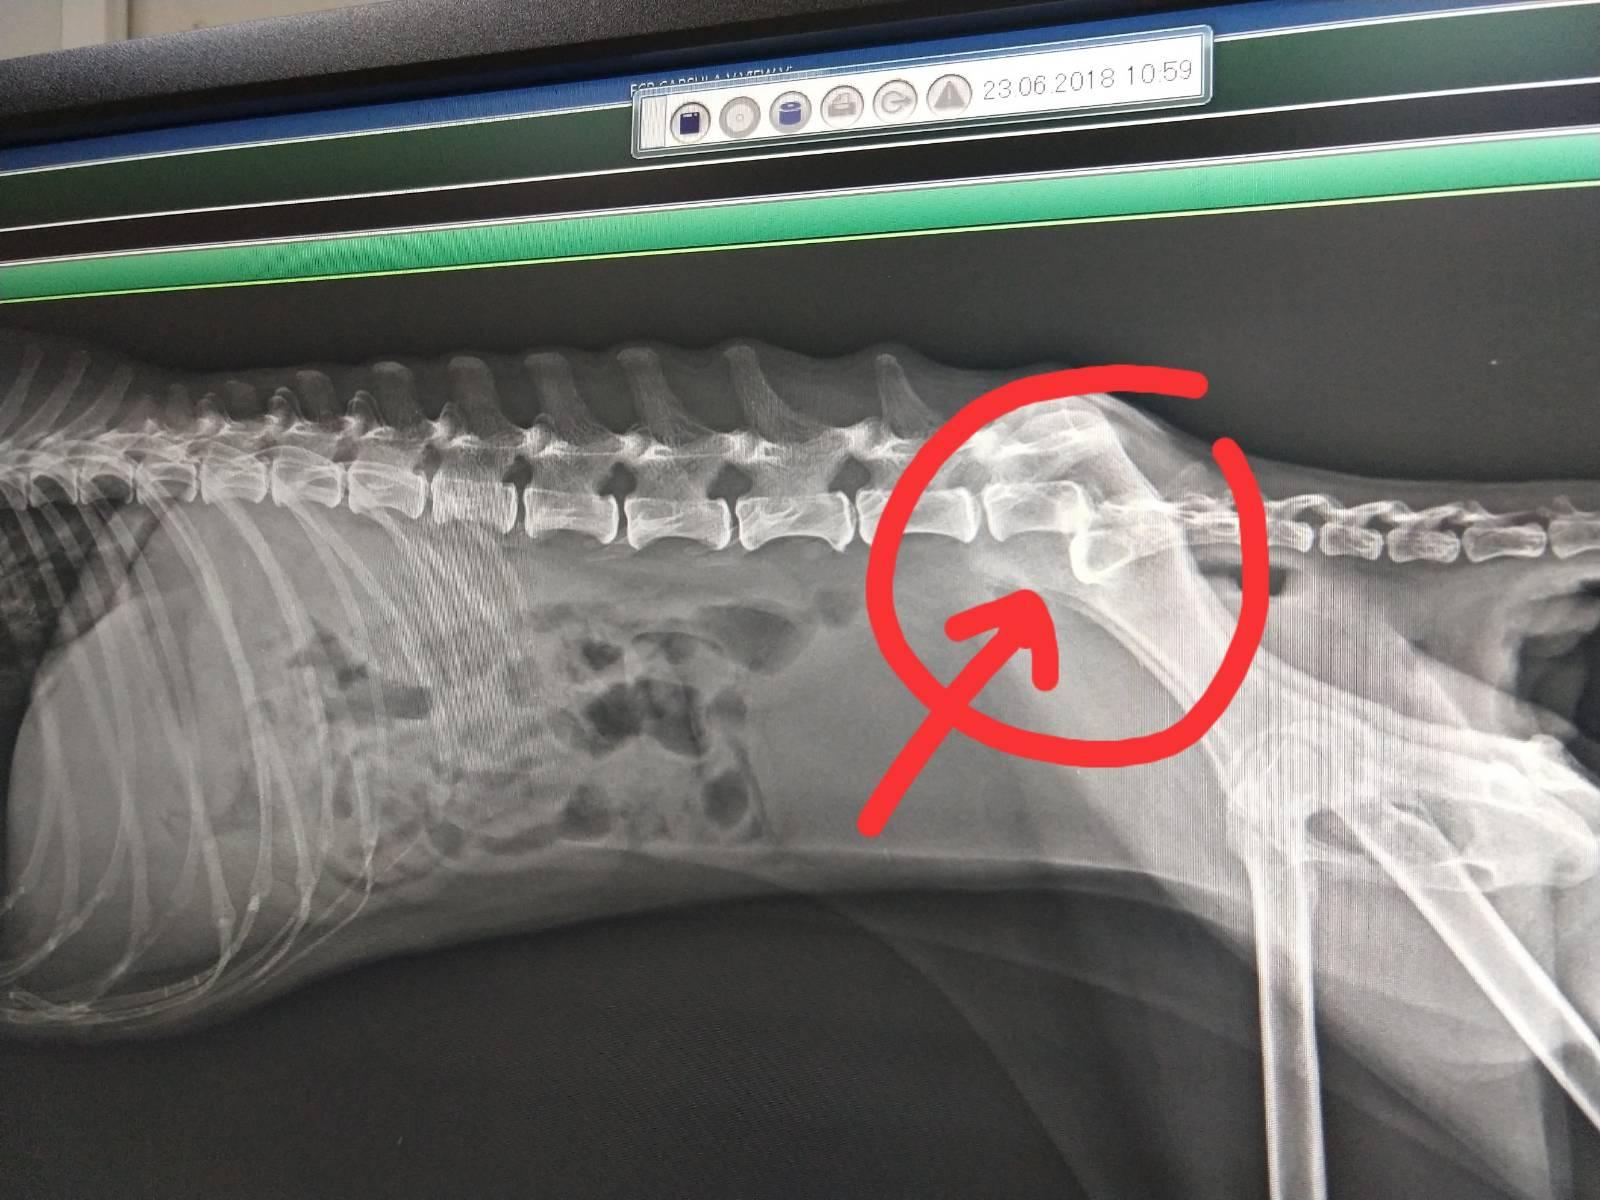

23 มิ.ย. เราพาโกกิไปรักษาที่รพส.สุวรรณชาด โกกิได้รับการเอ็กซเรย์ใหม่อีกรอบ (ดิจิตอล) และเจาะเลือดตรวจ(ปกติ) ที่ทำให้เราช็อคเมื่อตอนเห็นผลเอ็กซเรย์คือ โกกิกระดูกสันหลังหัก!!!!! ในส่วนที่เป็นการควบคุมขับถ่าย

เราเลยถามคุณหมอที่รพส.สุวรรณชาดว่า การหักของกระดูกนี้เป็นเพราะความเสื่อมสภาพตามอายุขัยหรือไม่ คุณหมอส่ายหน้าเบาๆ พร้อมกับบอกว่าต้องเกิดอะไรสักอย่างตอนที่โกกิรักษาตัวที่รพส.ที่หน้าปากซอยบ้านเรา เพราะเราเอาคลิปก่อนเข้ารักษาที่กทม.ให้หมอดูว่าหมาเรายืนได้เดินได้ปกติจริงๆ